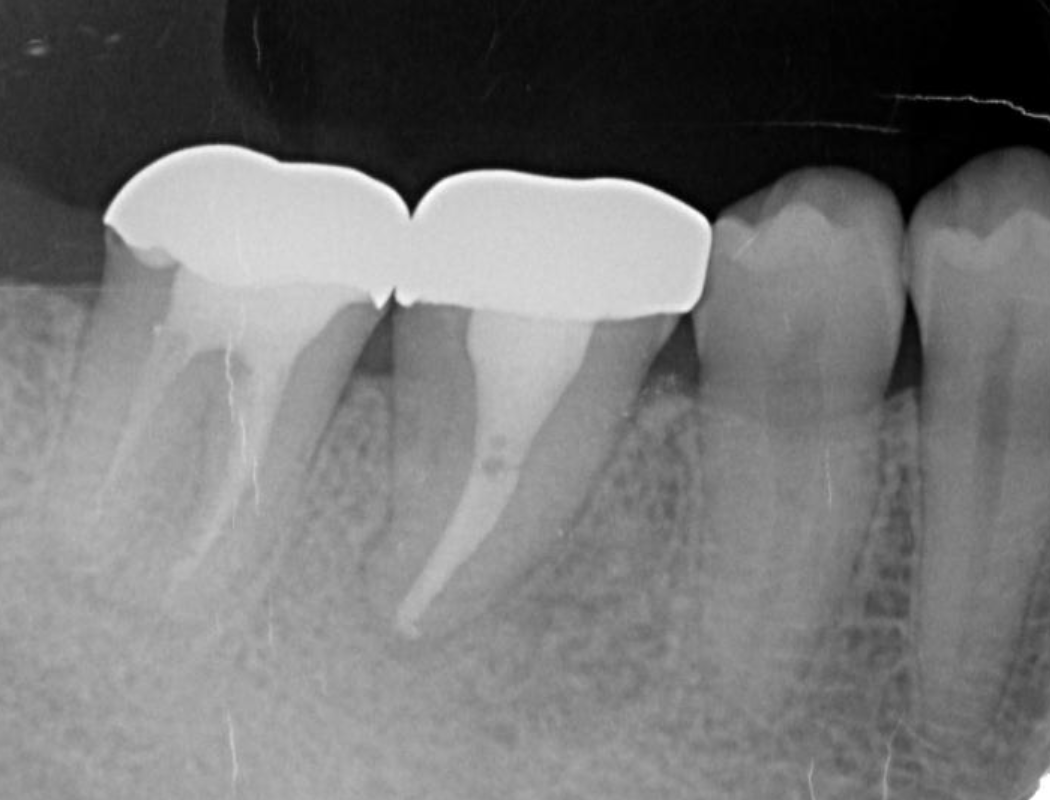

Bone regeneration was confirmed before and after grafting, after root filling, and after placement of the prosthesis, based on X-ray imaging results (Figure 8). There was no pathologic mobility or pain during mastication, and the tooth showed good function. The patient was very satisfied with the treatment results (Figure 9).

Figure 8.Cone beam CT image obtained after transplantation. Bone regeneration around the grafted tooth was confirmed.

Figure 9.Dental X-ray image obtained two years after transplantation. Bone regeneration around the grafted tooth was confirmed.

Following the operation, root canal treatment was performed as noted above. Functions including temporary crown occlusal contact and tooth mobility, as well as pocket depth were also checked. All examination results clearly indicated placement of a definitive prosthesis in the patient (Figure 13, Figure 14). At a follow-up examination one year after surgery, progress in this case was determined to be good (Figure 15).

Figure 13.Dental X-ray image obtained after confirmation of definitive prosthesis. Bone regeneration can be seen around the root of the donor tooth.